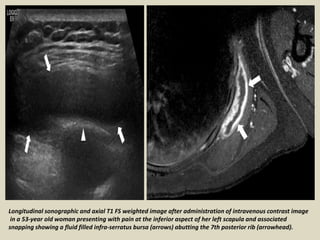

Longitudinal sonographic and axial T1 FS weighted image after administration of intravenous contrast image

in a 53-year old woman presenting with pain at the inferior aspect of her left scapula and associated

snapping showing a fluid filled infra-serratus bursa (arrows) abutting the 7th posterior rib (arrowhead).